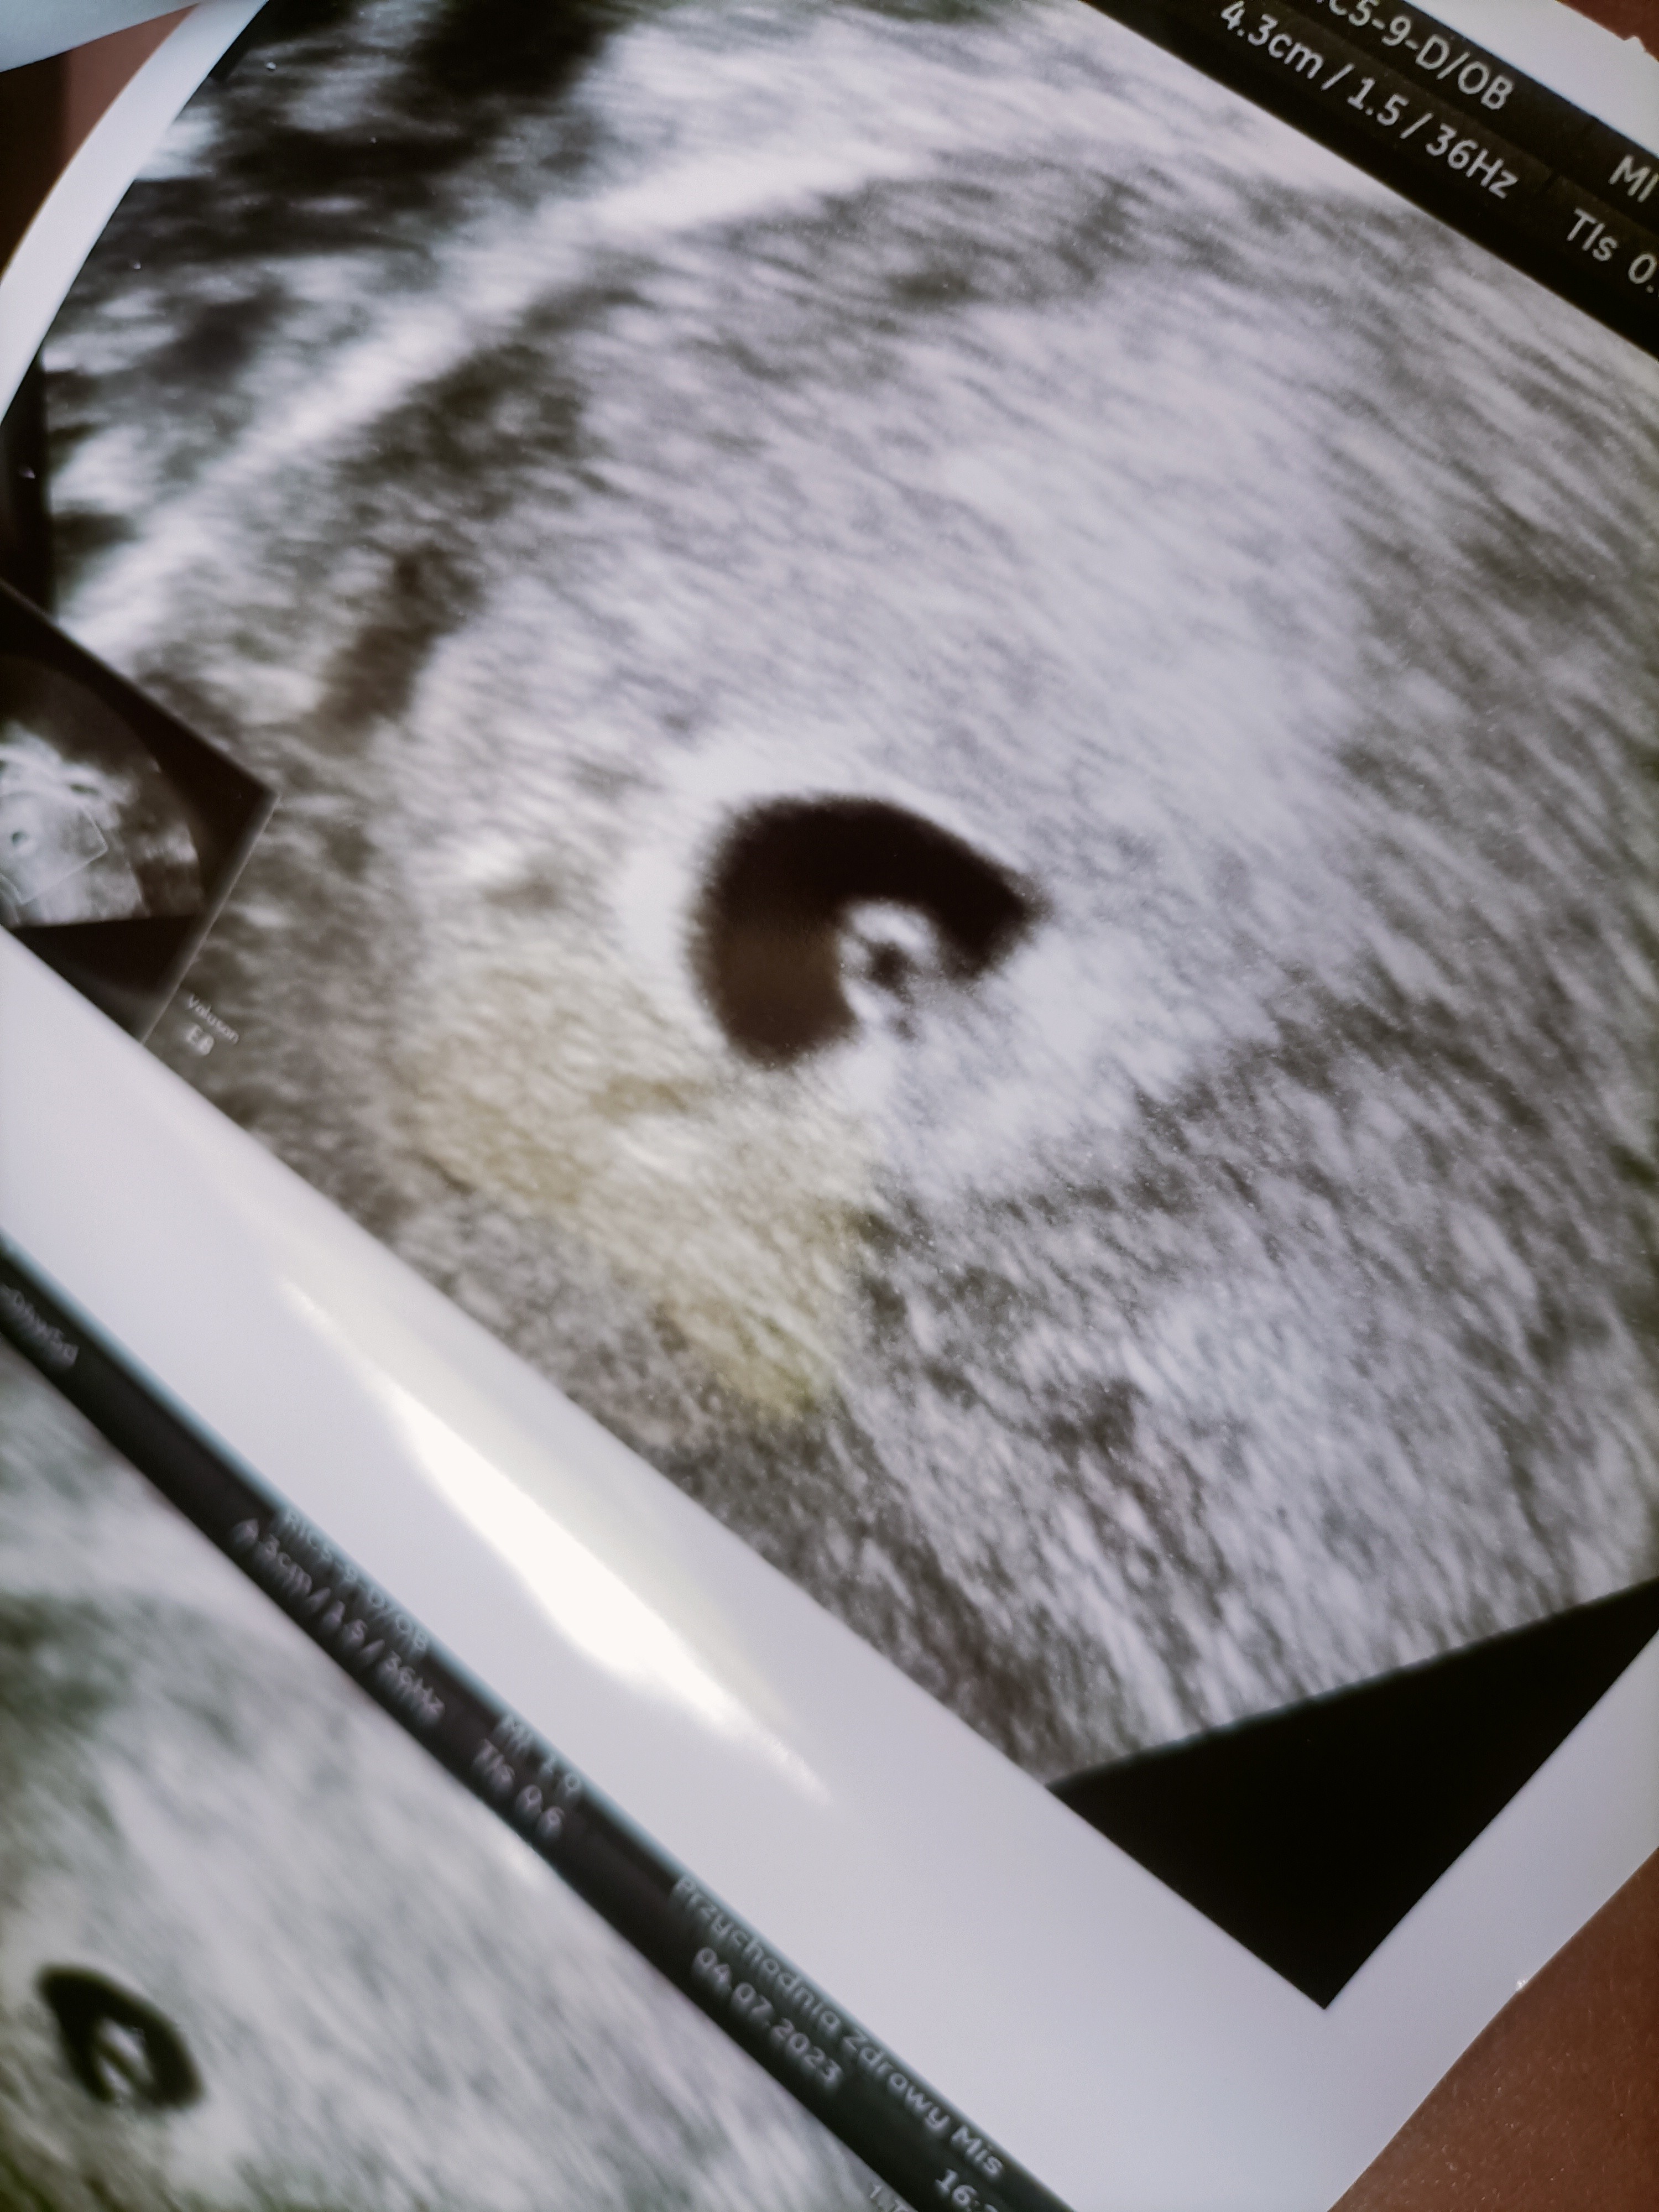

Ja już po wizycie...

Na USG było widać pęcherzyk ciążowy który jest dobrze umiejscowiony 🥹

Kolejna wizyta za 2 tygodnie - wtedy będzie widoczne serce ❤️ ...

Ja już po wizycie. Nigdy nie myślałam że będę zadowolona z kobiety ginekologa :)

Do sedna jest moja mała kropeczka. Wygląda wszystko w porządku.

Następna wizyta serduszkowa 21.07 . Do tego czasu mam zrobić USG piersi i milion badań w tym chyba HIV grupę krwi toksoplazmozę i chyba prawie wszystko.